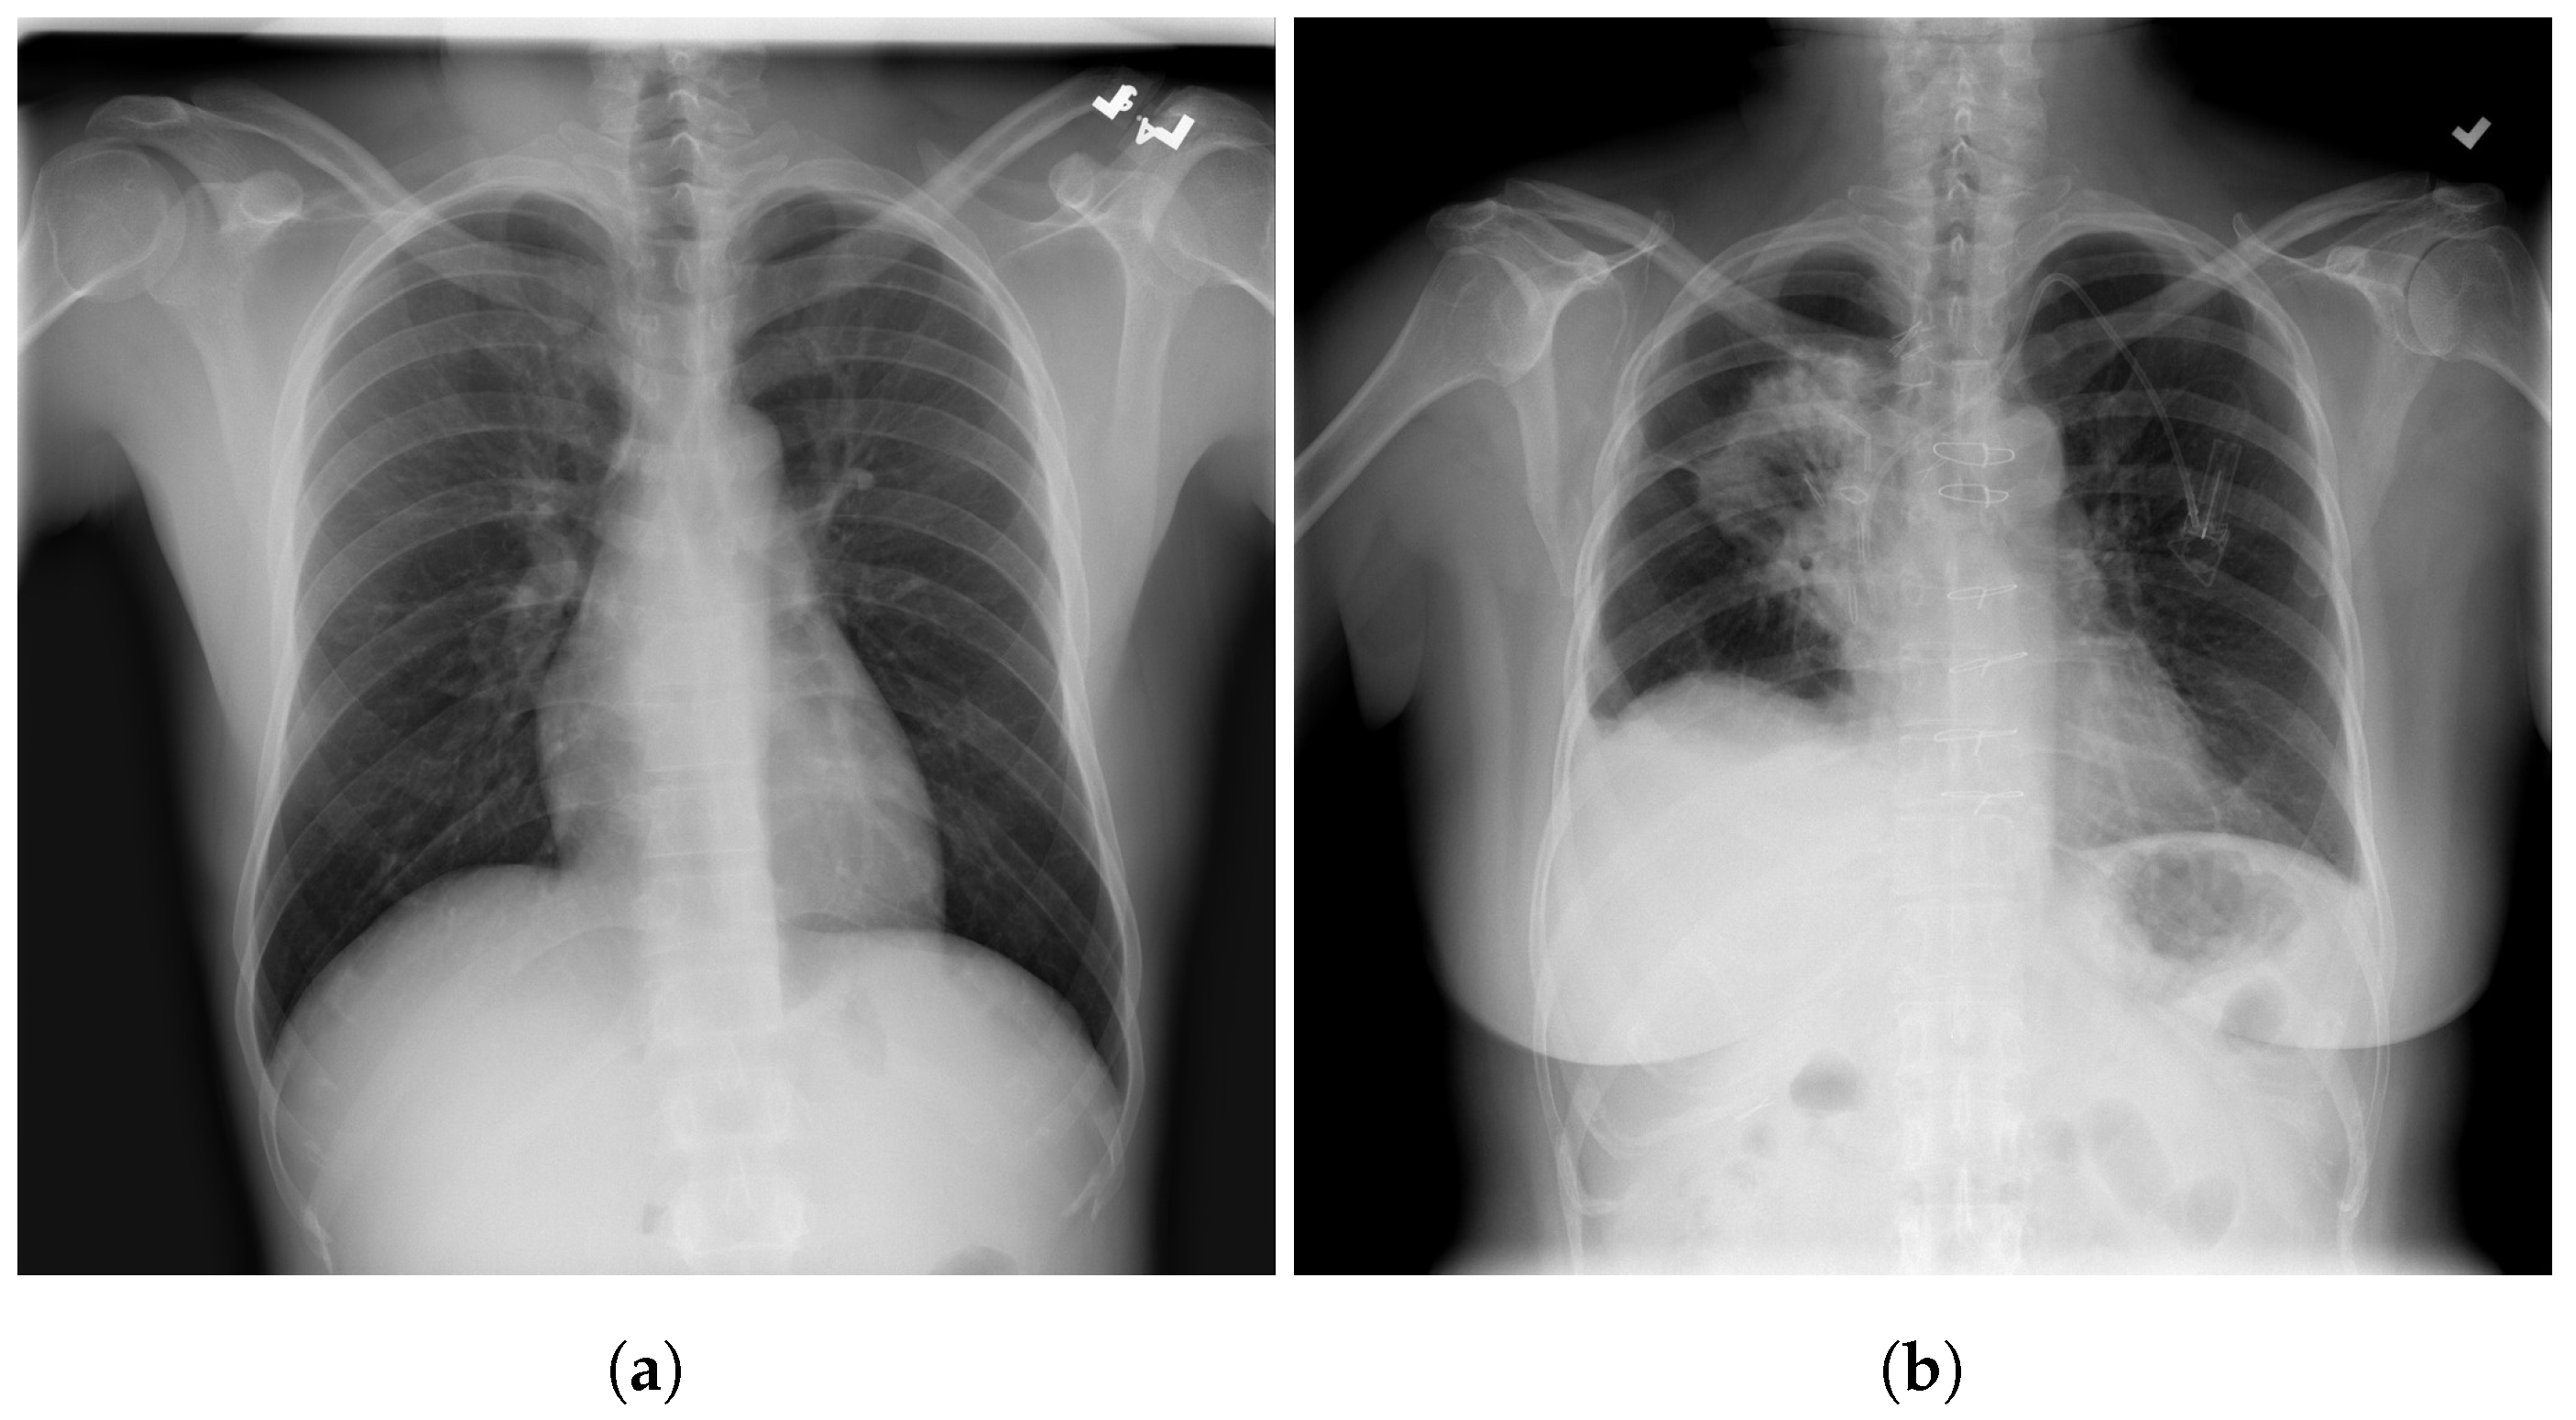

3.1. COVID-19 Image Data Collection (CIDC)

3.2. COVID-19 Radiography